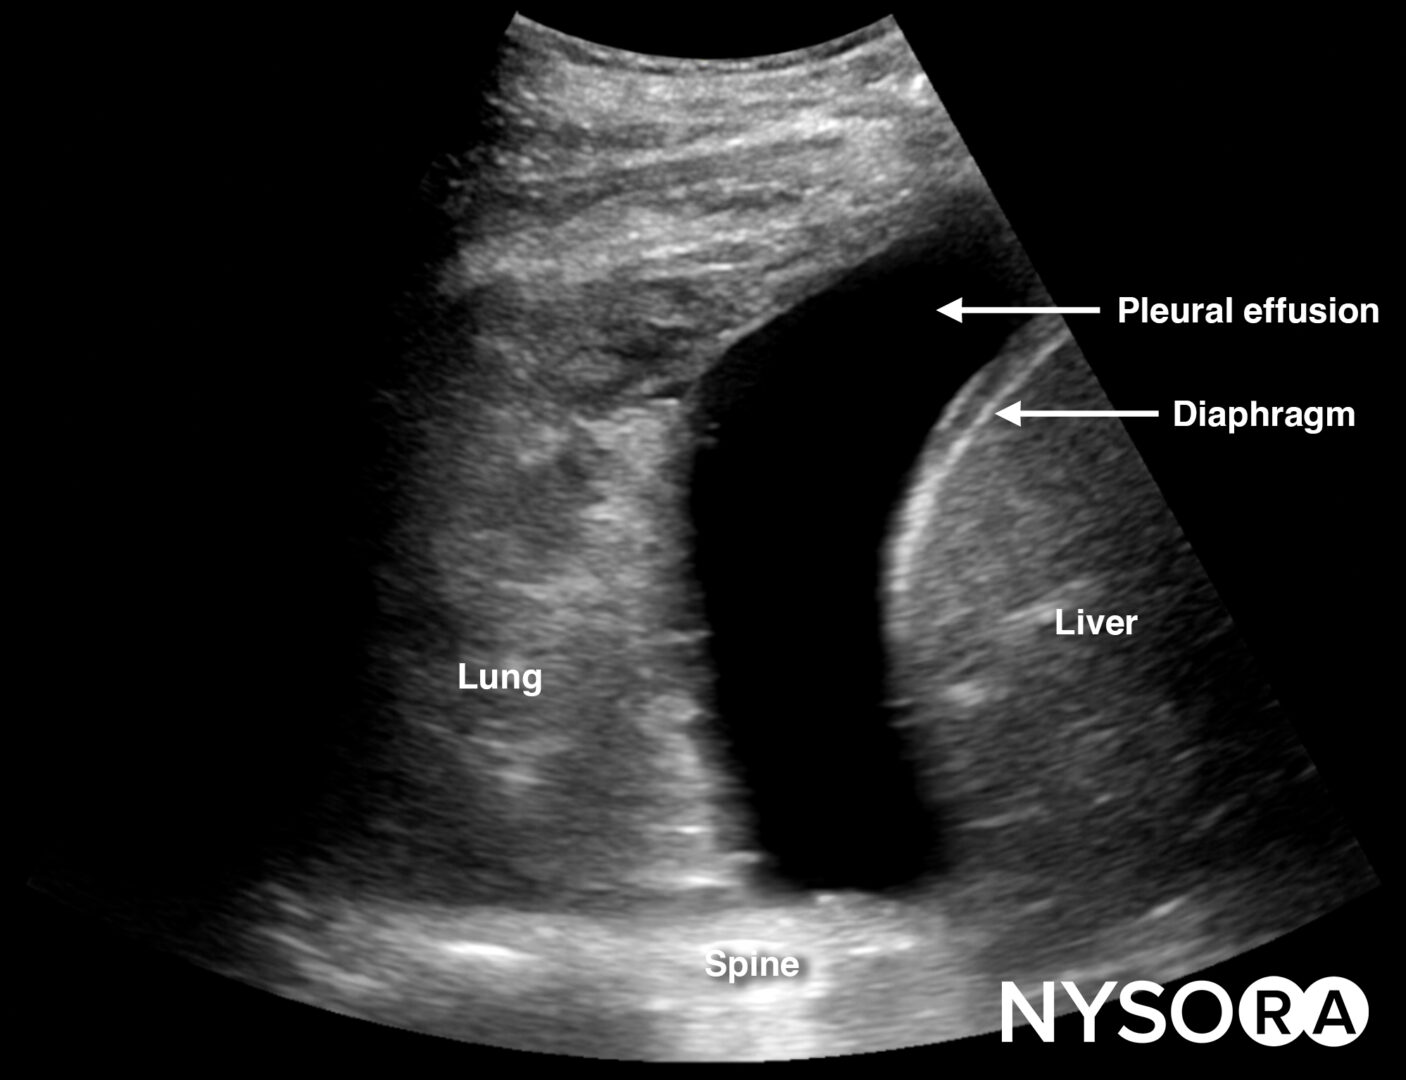

Free right intraperitoneal fluid collects between the liver and the kidney (Morrison’s pouch). If intrathoracic free fluid is present, it can be identified above the diaphragm.

Always assess the area above the diaphragm for free fluid in the RUQ and LUQ.

Free fluid or pleural effusion above the diaphragm.